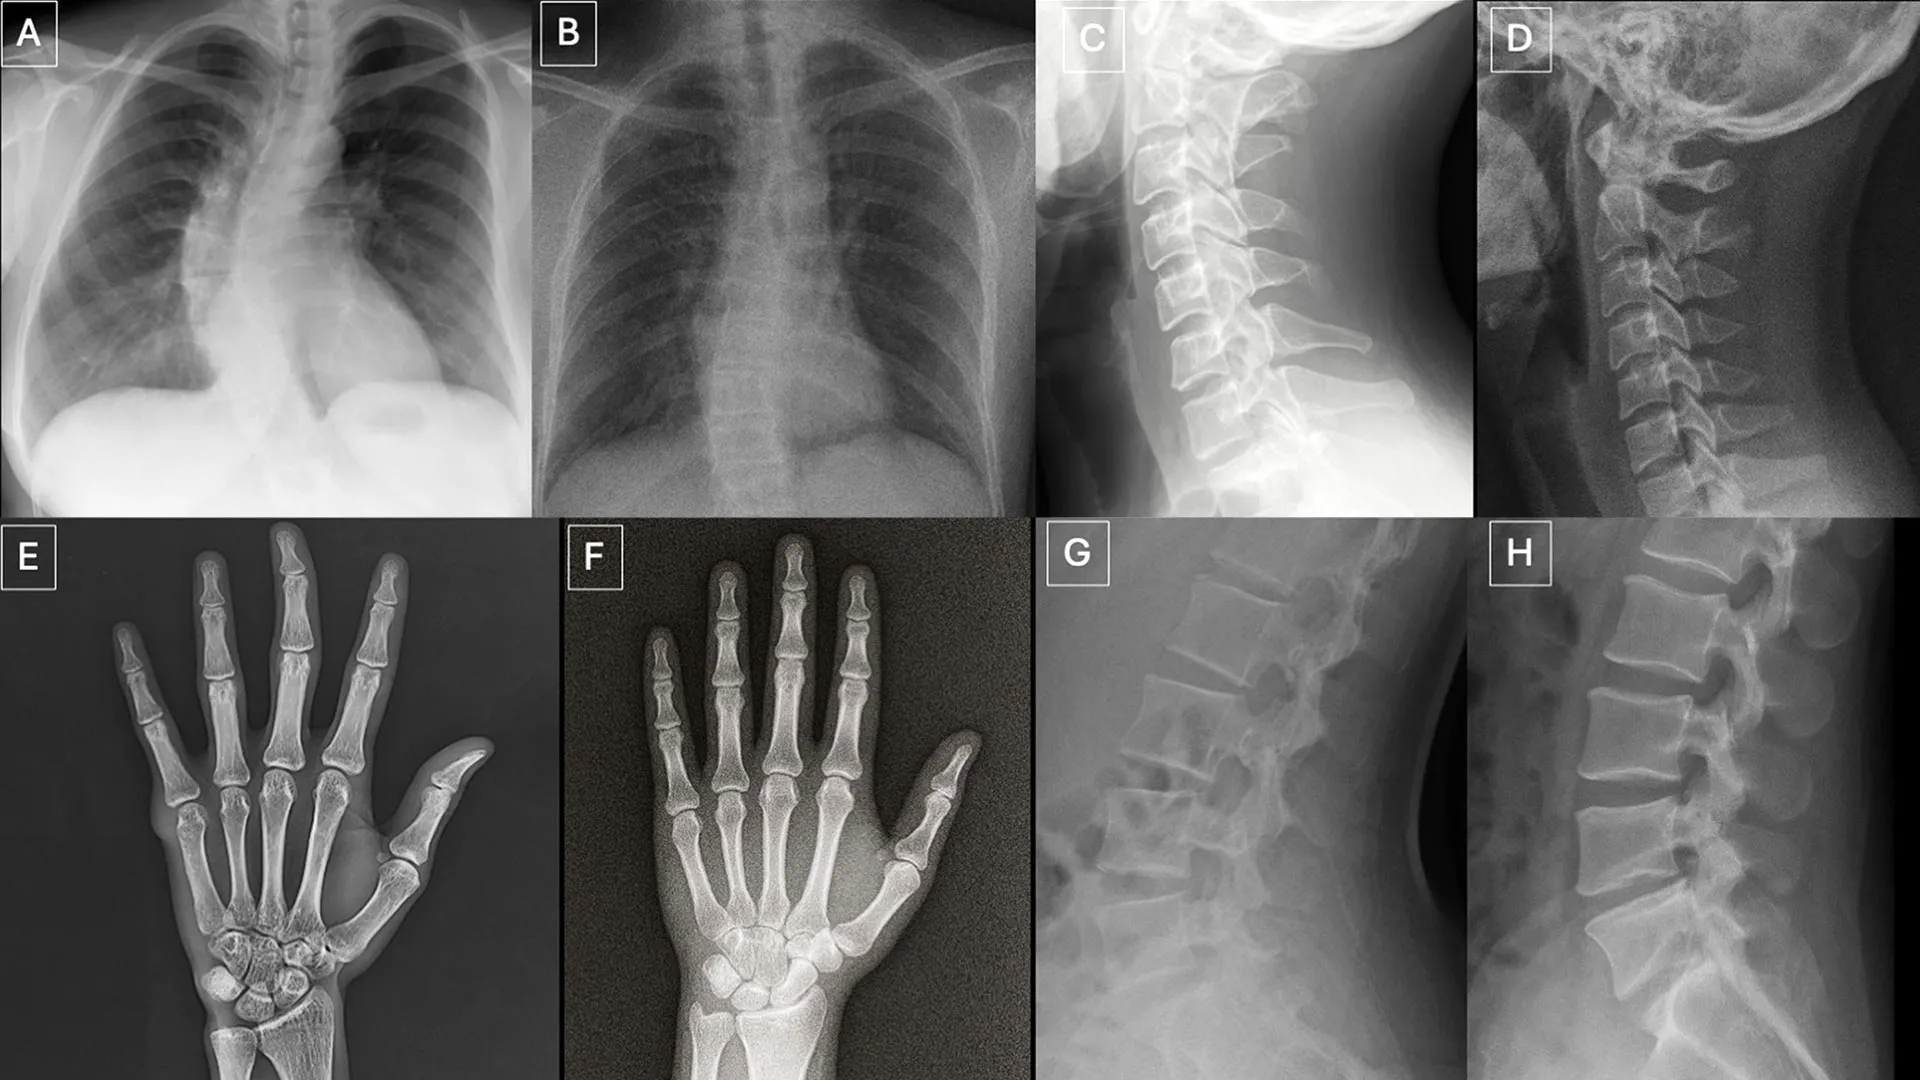

Participants reviewed two separate image sets with no overlap. One set contained a mix of real images and ChatGPT-generated X-rays from different parts of the body. The second set focused on chest X-rays, with half real and half created using RoentGen, an open-source generative AI diffusion model developed by Stanford Medicine researchers.

Researchers identified several patterns that can appear in synthetic images.

"Deepfake medical images often look too perfect," Dr. Tordjman said. "Bones are overly smooth, spines unnaturally straight, lungs overly symmetrical, blood vessel patterns excessively uniform, and fractures appear unusually clean and consistent, often limited to one side of the bone."